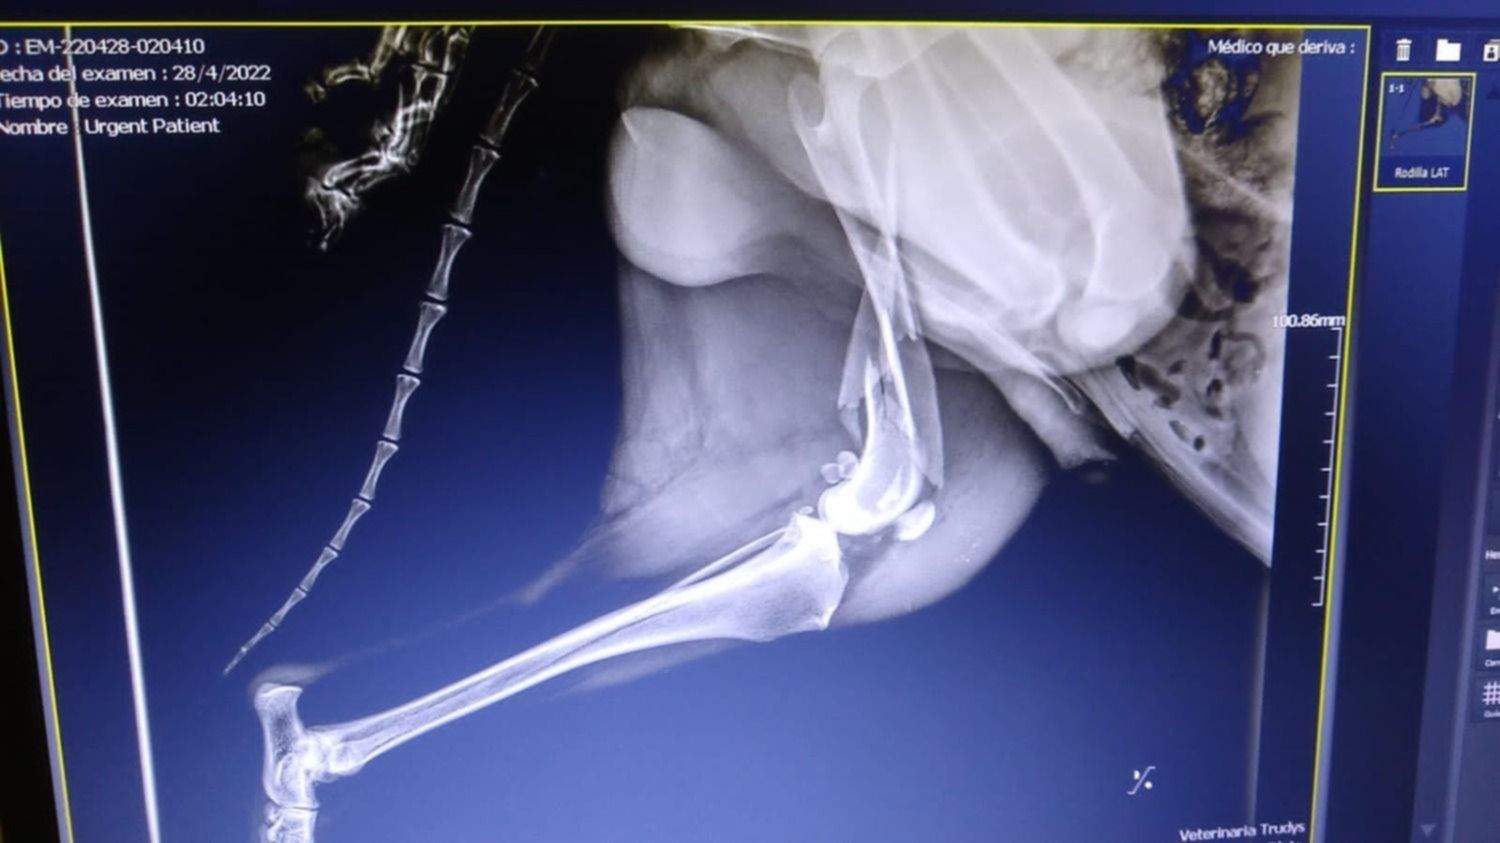

En ese sentido, detallaron que los especialistas le hicieron una serie de análisis de sangre en donde le diagnosticaron que tiene "hemoparásitos y debe comenzar con urgencia el tratamiento" para luego ser operado.